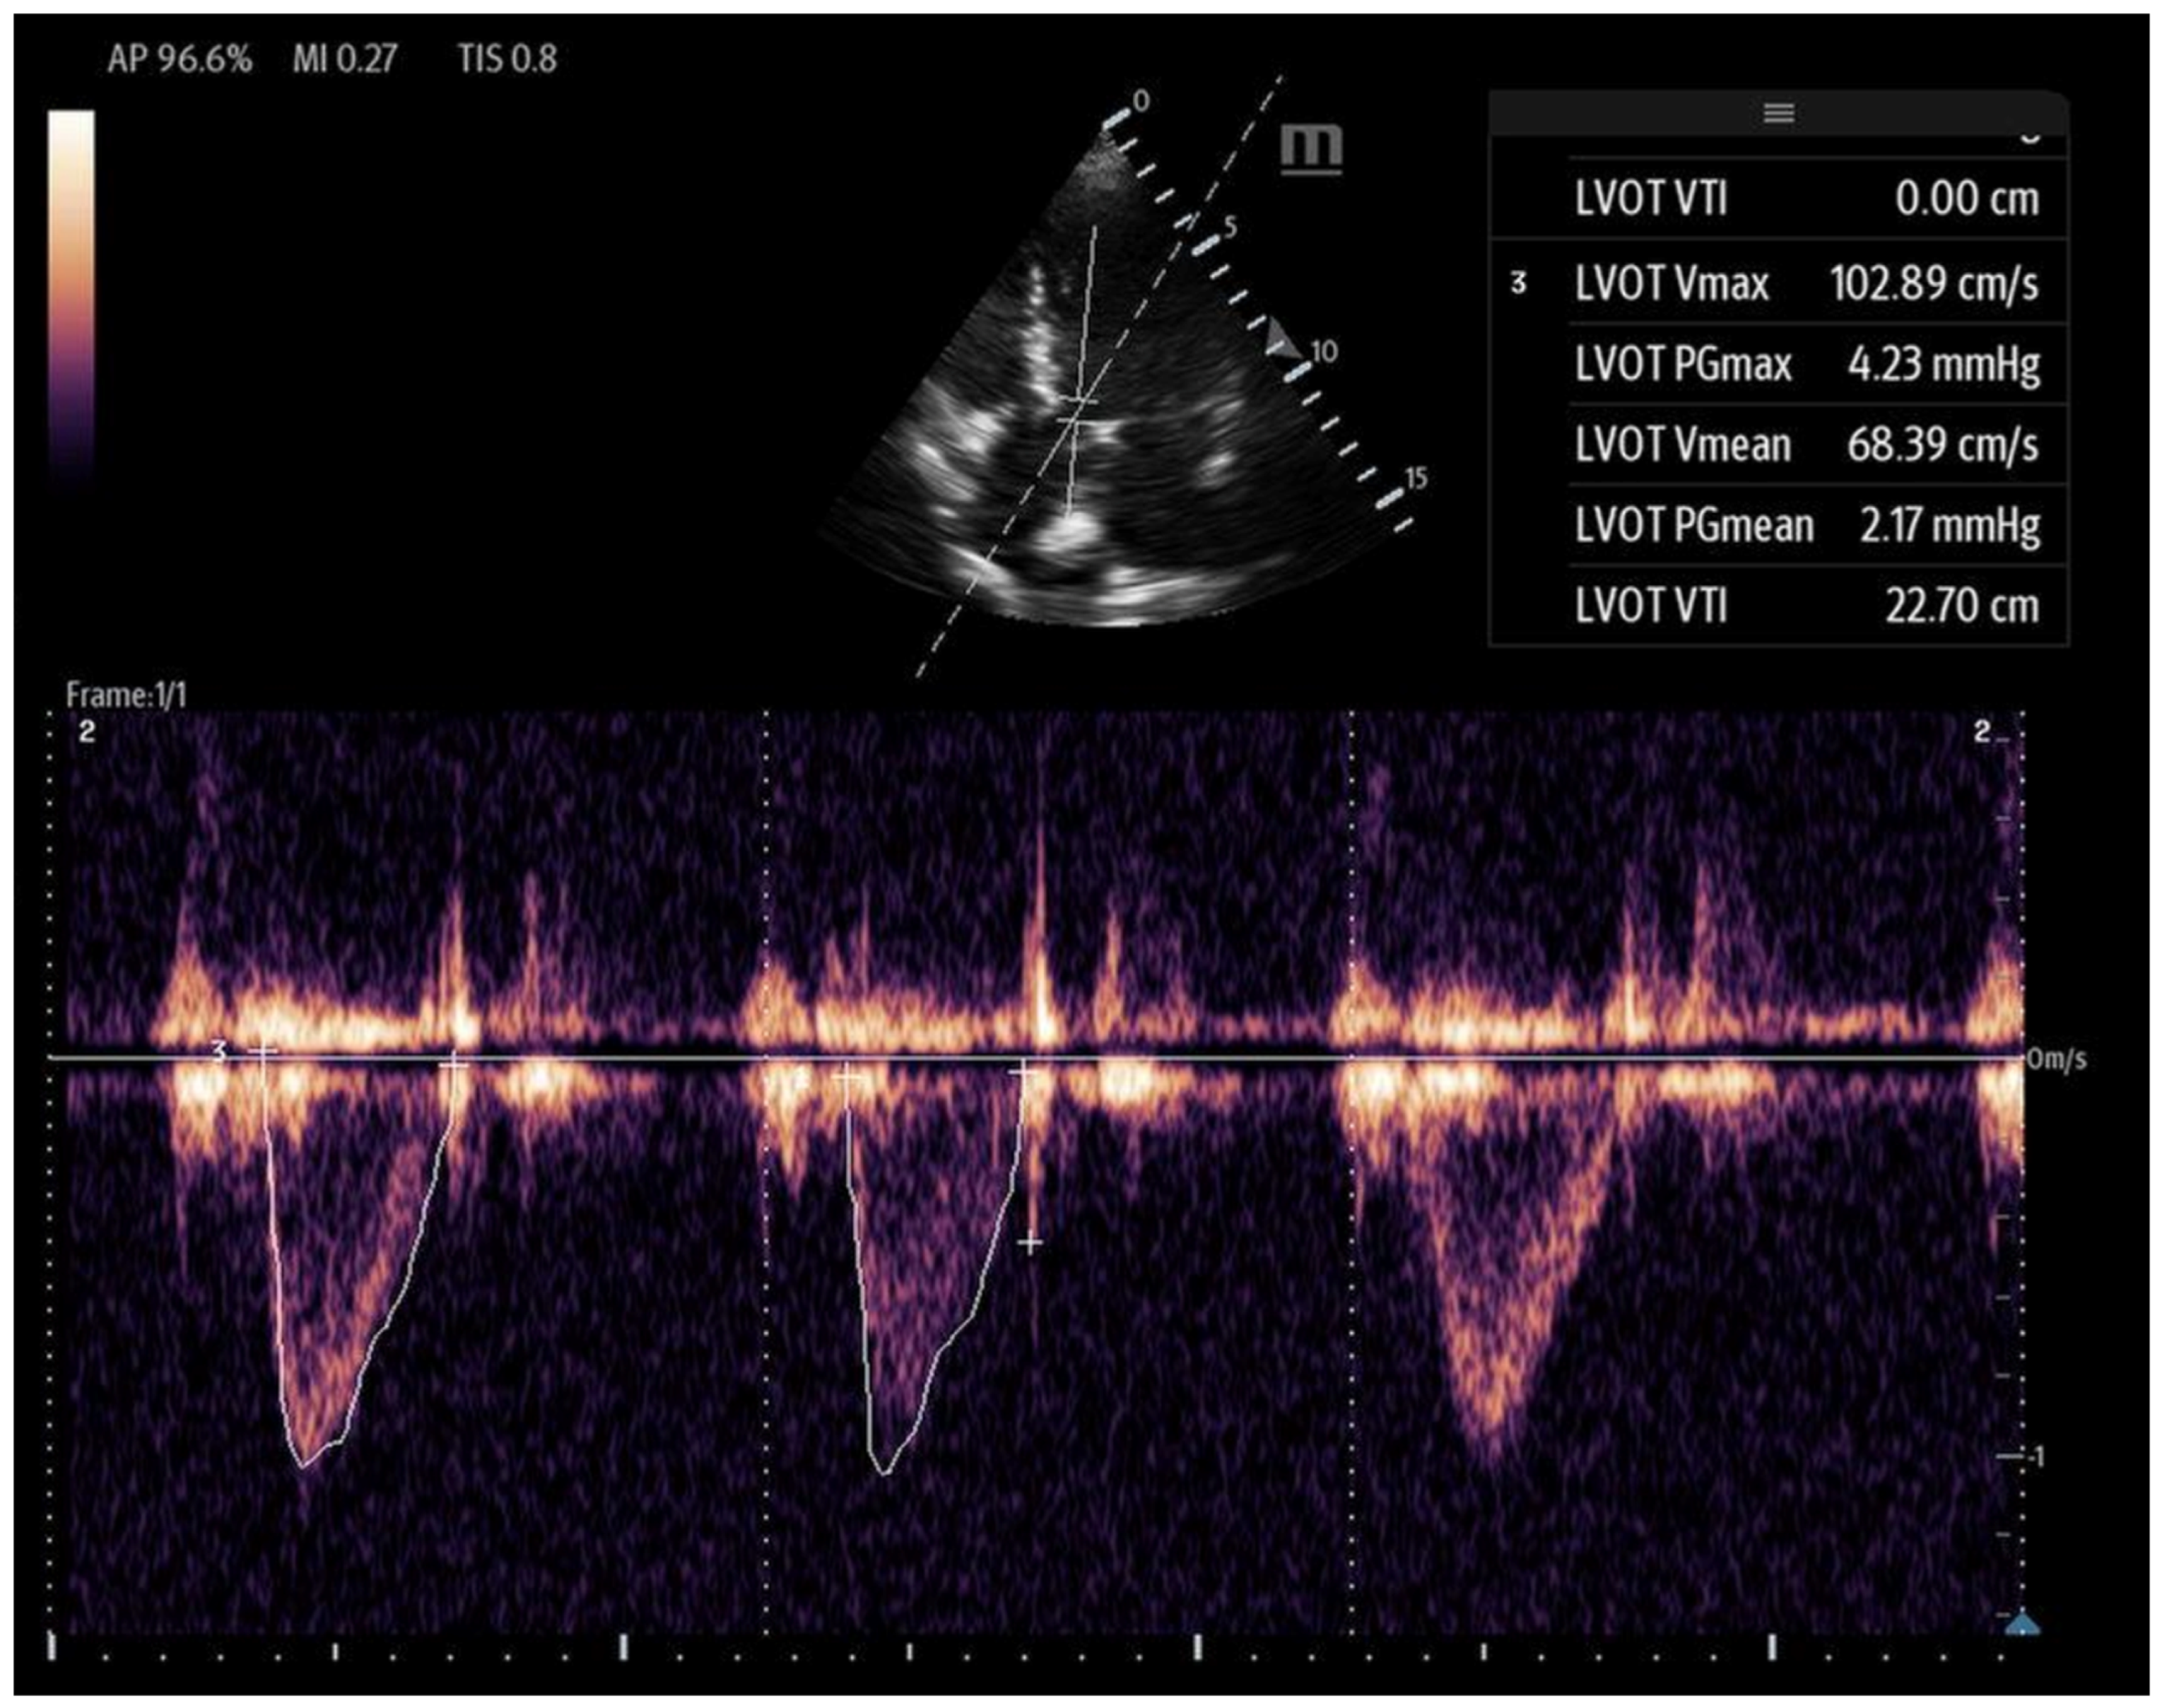

4.2.2. Left Ventricular Velocity–Time Integral (LVOT-VTI)

In hemodynamically unstable patients, the LVEF may not reliably reflect SV in hyperdynamic conditions, and a high LVEF can be accompanied by reduced SV, whereas patients with a severely reduced LVEF may still have normal SV [59]. SV offers real-time data on the effectiveness of interventions like inotropes and is crucial for calculating CO, making it one of the most accurate echocardiographic markers for estimating SV and CO [60]. Additionally, SV is a marker of preload sensitivity, which will be discussed further below.

To estimate SV and CO, ultrasound requires two key measurements: the LVOT diameter and the LVOT-VTI. Cardiac output can also be indexed to body surface area to calculate the cardiac index (CI), further enhancing the hemodynamic assessment.

The LVOT diameter is measured in the PLAX view, focusing on the LVOT and aortic valve when maximally open during mid-systole (Figure 12). The measurement is taken at the base of the aortic valve, and the area is calculated using the formula:

The VTI is measured in the apical five-chamber view using pulse-wave Doppler, with the sample volume placed at the center of the LVOT to trace the velocity curve (Figure 13). The VTI, measured in centimeters and averaged over several beats to account for beat-to-beat variability, reflects the distance that blood is propelled forward from the LVOT to the aorta with each contraction. When used in conjunction with blood pressure and lactate levels, the LVOT-VTI can help guide shock etiology as well. A low VTI with hypotension and elevated lactate suggests low-output shock (e.g., cardiogenic), and a high VTI with hypotension and elevated lactate may suggest distributive shock (e.g., early sepsis). The normal range is between 17 and 23 cm, and it serves as a surrogate for stroke volume. When used in conjunction with the clinical picture, the VTI can also serve as a valuable tool for longitudinal assessment and is shown to decrease total time on vasoactive agents [61].

Figure 13.

Left ventricular VTI calculated with PW Doppler with Doppler gate at LVOT.